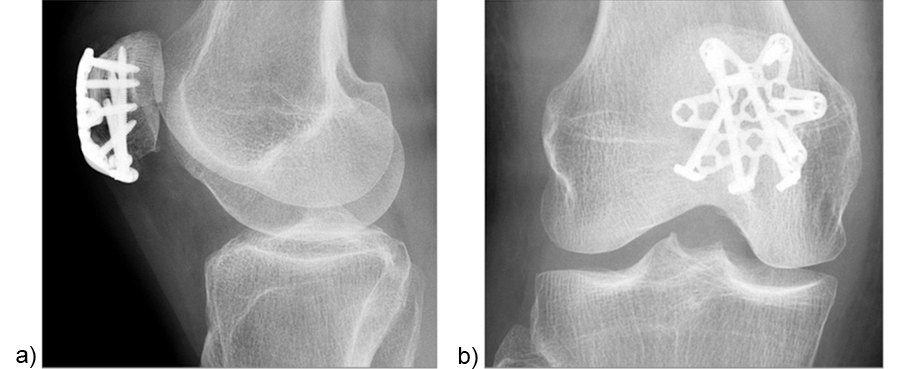

Treatment of a fragmented distal pole patella fracture with a three-hole patella plate (by Christoph Sommer, Kantonsspital Chur, Switzerland).

A 73-year-old woman sustained a right 34-C3.1 patella fracture during a hiking injury (Fig 1). X-ray analysis revealed that the distal pole was fractured in four fragments (Fig 2). After fracture reduction, a three-hole plate was used with three inferior to superior locking screws in the coronal plane through the holes of the plate legs and five anterior to posterior locking screws (Fig 3 and Fig 4).